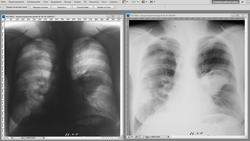

3.Сравниваем, довольные собой:

4.Можно там же использовать инверсию: